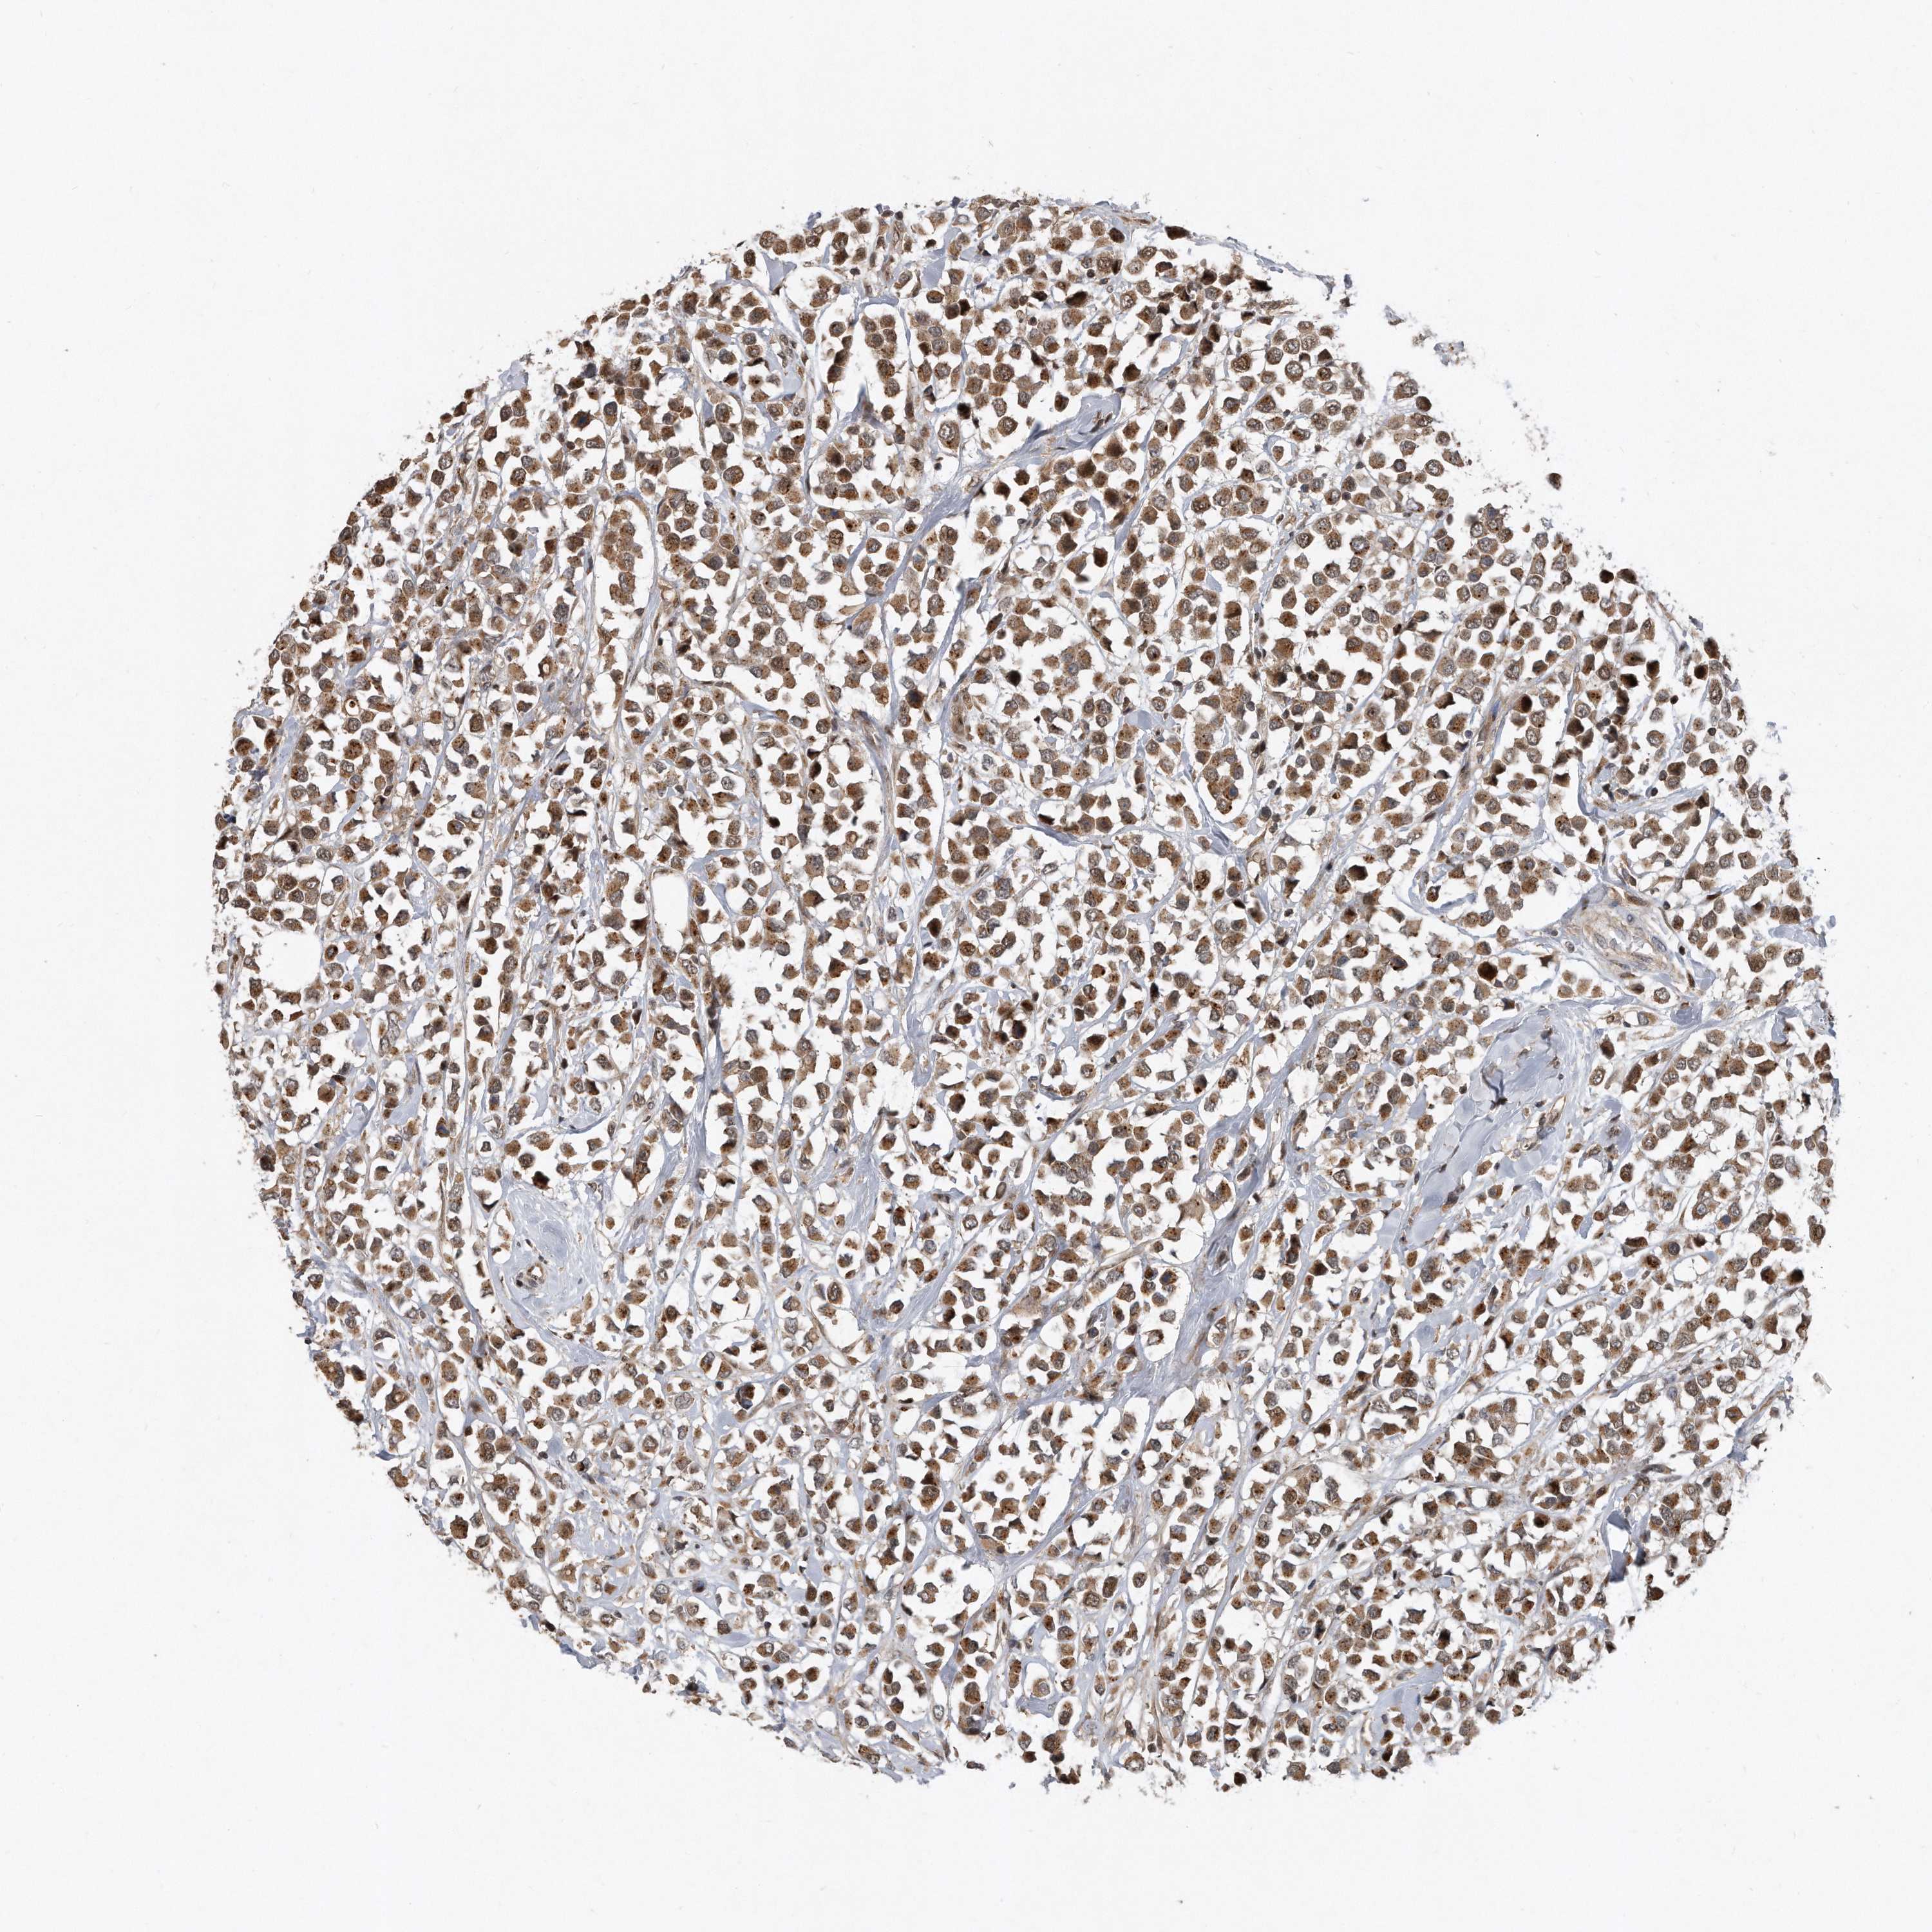

BRCA TCGA BRCA VALIDATION PROTEIN EXPRESSION

ANTIBODIES

AND

VALIDATION